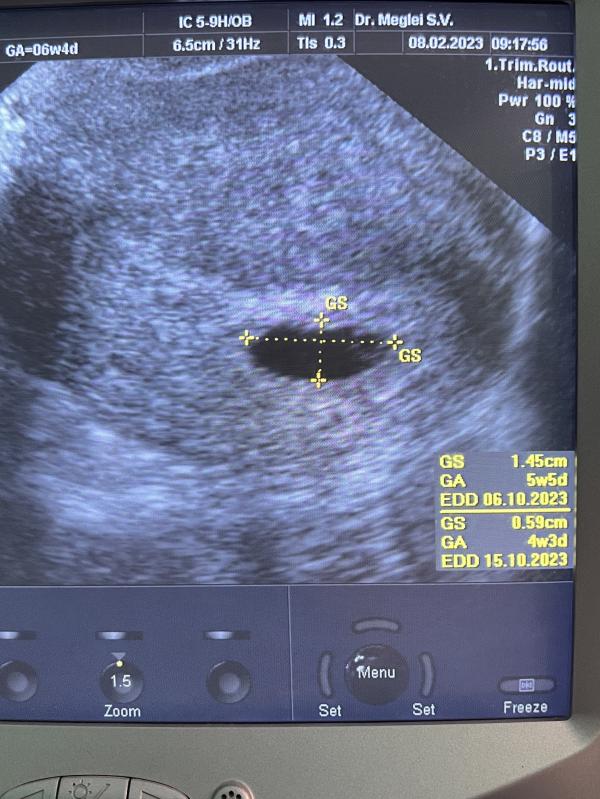

Сегодня была на первом узи) по акушерским всего 5 недель и 4 дня🥰

Врач сказал, что пдр на 6 октября) овуляция была поздняя) да и в целом овуляции происходили не каждый месяц 🤔

@snezhanaprivet, у меня срок 5н поставили пя 6.6 , жм 1,5